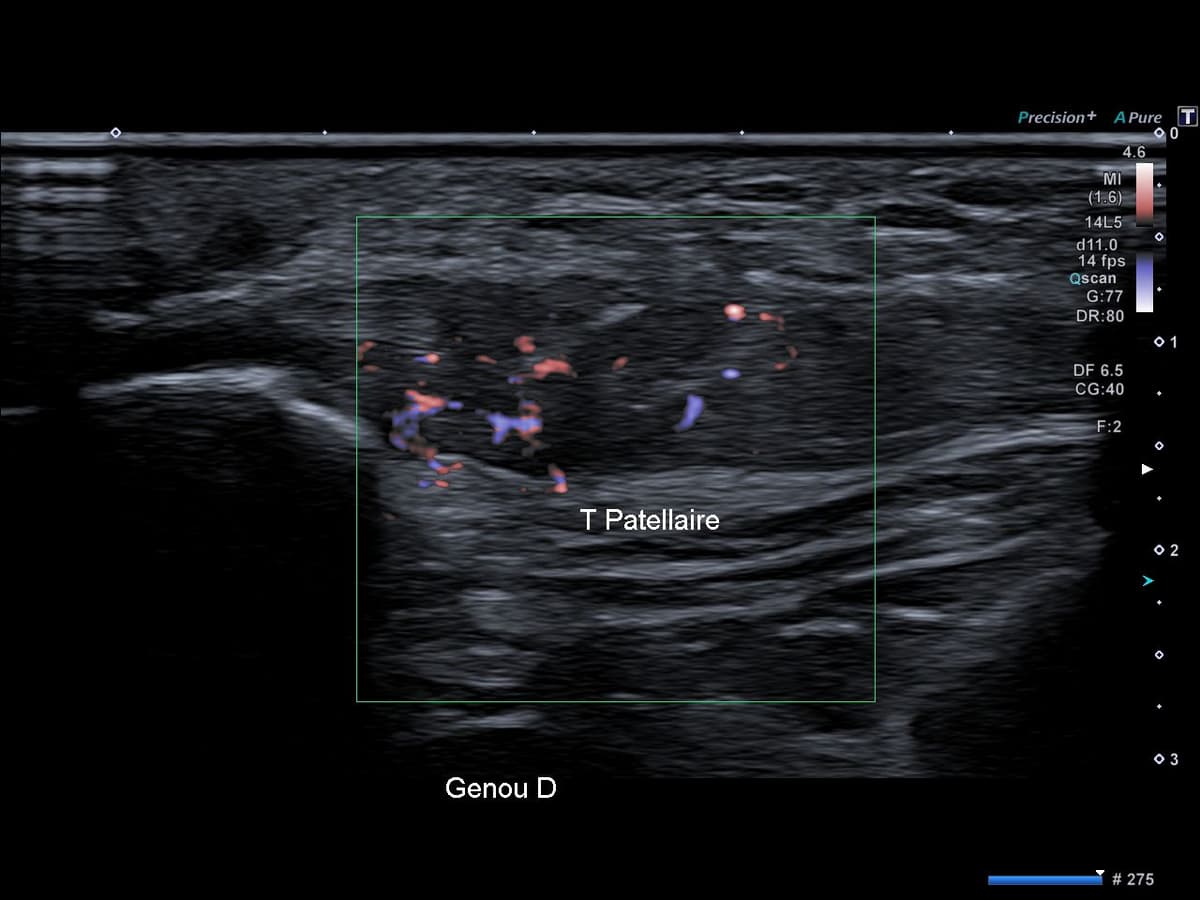

Basketteur professionnel asymptomatique, découverte fortuite d'une séquelle de "Jumper's Knee".

US